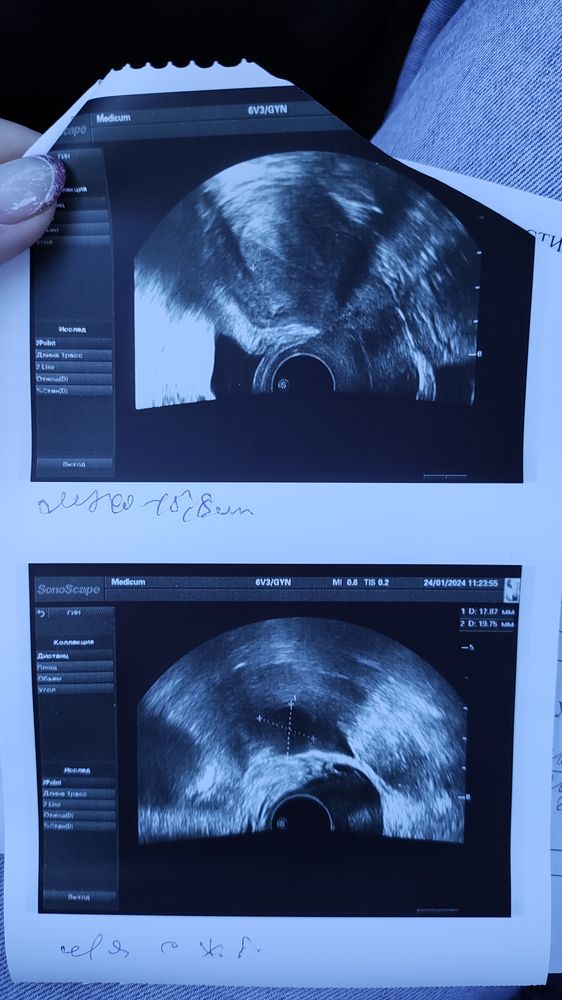

Сходила я сегодня на УЗИ. Лучше бы не ходила. В матке ничего нет. По последним М пять недель. Но факту гораздо меньше. Узистка говорит, что была поздняя овуляция. Числа 9 ПА был 7. Первая бледная полоска была 16 января. И скорее всего это был день прикрепления. Эндометрий хороший, ЖТ в левом яичнике. Я уже перепугалась за бхб. Купила эвик домой, а там почти сравнялись полосочки.